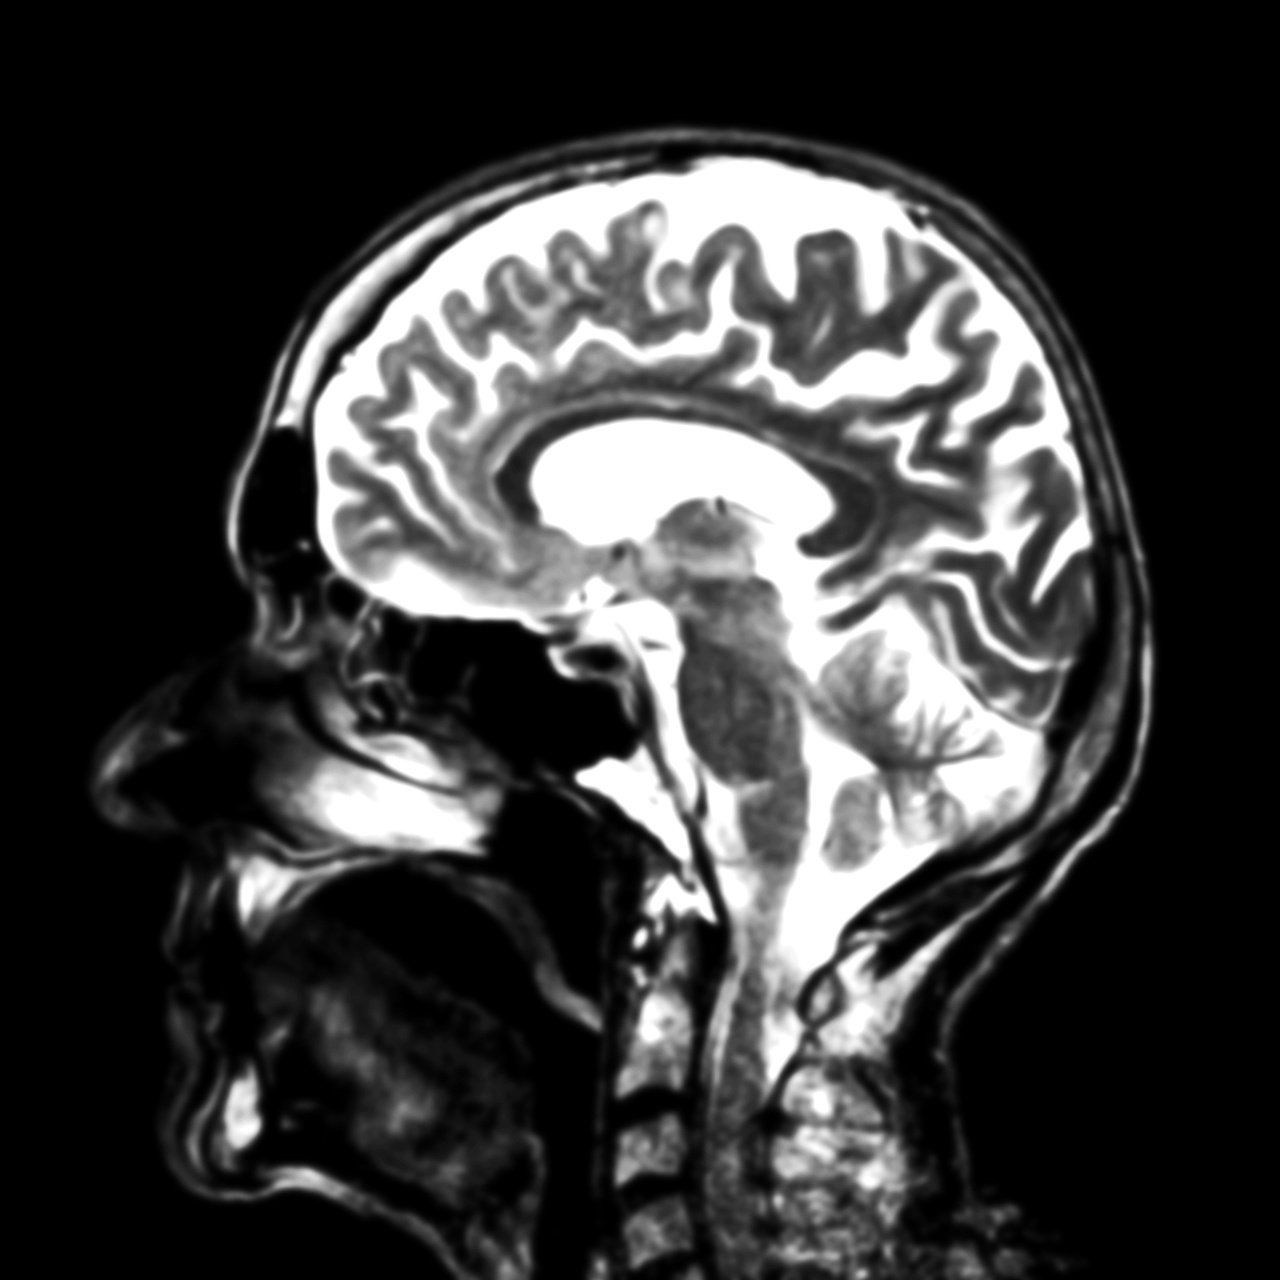

To give you an example, below I’ve inserted three models of the same thing: a nucleosome. Each of these was clearly developed to emphasize a particular relationship between structure and function. But those relationships lie at different scales, which has dictated the level of detail that is included, what lies in the foreground and background, and influenced all sorts of stylistic decisions.